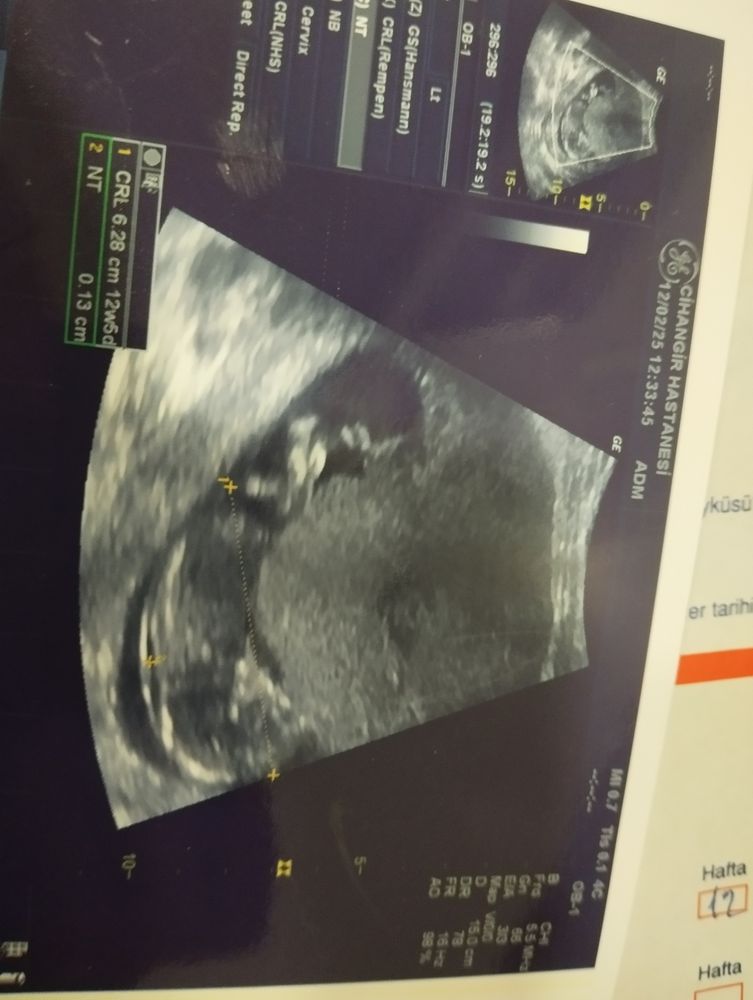

Севда в Клуб беременных 10 месяцев Кто разбирается кто там Пол малыша Кто видет пол ребенка как то отличается я не разбираюсь в этом (( Посмотрите еще 20 записей на эту тему Отменить Ответить Людмилка Ножки лежат так, что бугорка не видно вообще, да и фото не для рассматривания ТК врач сделал фото, когда мерял ктр ребёночка. 12.02.2025 Ответить Севда Людмилка, как на зло 12.02.2025 Ответить Домашнее гендер пати😅 Фото) Как думаете, мальчик или девочка Чаты Беременных Выберите чат: Январята-2026 Февралята-2026 Мартята-2026 Апрелята-2026 Майчата-2026 Июнята-2026 Июлята-2026 Августята-2026